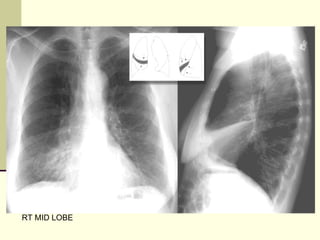

RT MID LOBE

RT ML CONSOLIDATION